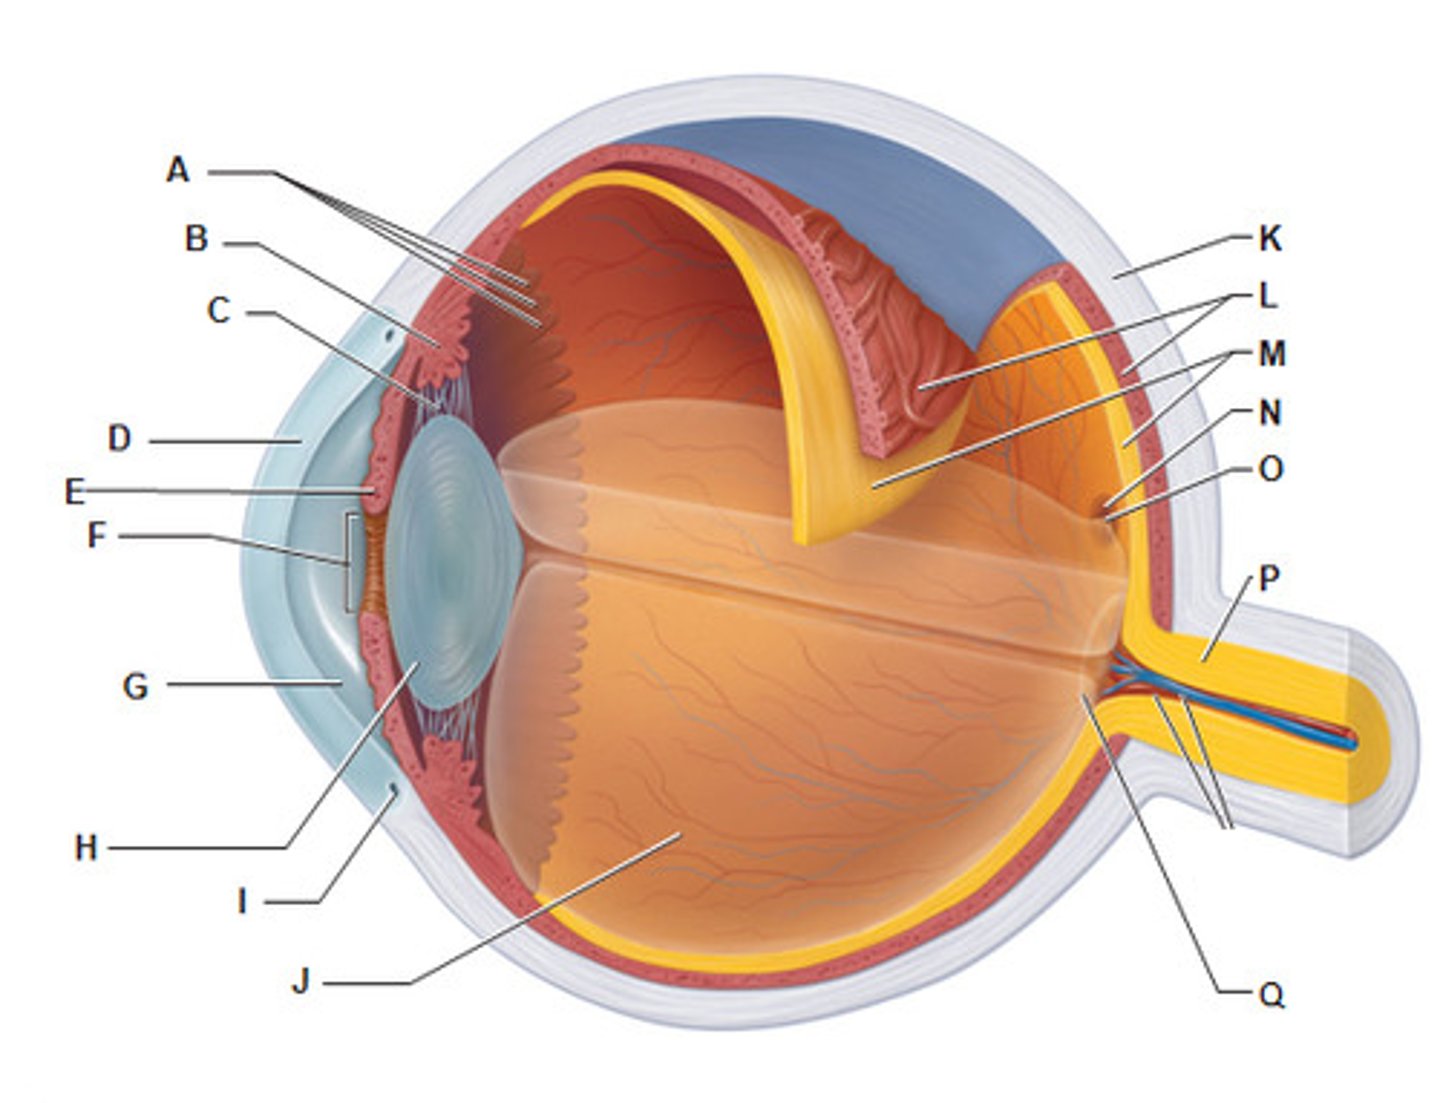

anterior cavity (of eye)

iris

B

optic disk (blind spot)

choroid

L

ciliary body

B

ciliary process

conjunctiva

cornea

D

fovea centralis

suspensory ligaments

C

vitreous humor

lens

H

macula lutea

nasolacrimal duct

lacrimal gland

posterior cavity (of eye)

pupil

F

retina

M

sclera

optic nerve